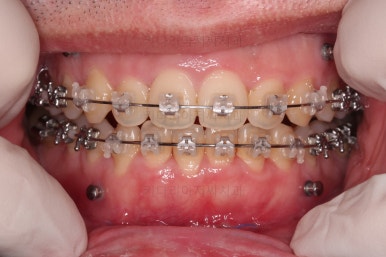

부산긴얼굴긴턱교정 수술 직후의 모습입니다.

아직은 붓기가 있고 입 벌리기도 힘들지만 매우 성공적이어 보입니다.

술전 교정 + 양악수술계획/협진 + 양악수술 이 삼박자가 잘 맞으면 술후교정은 일사천리로 진행됩니다.